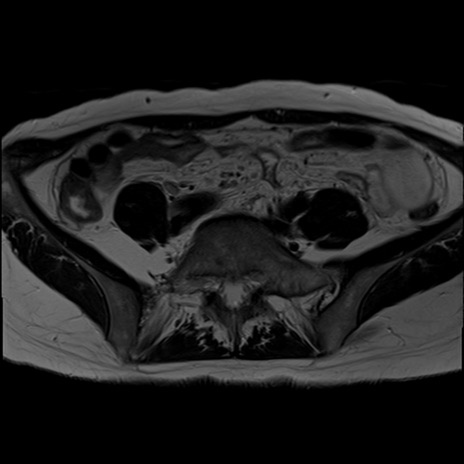

症例39 T2WI(横断像)

【症例】40歳代女性

【主訴】上下腹部痛

【現病歴】2日目から下腹部痛あり。夜間は痛みで眠れなかった。昨日より上腹部痛と下痢が出現。臥位で痛みは軽快したため、休んでいた。本日になって臥位でも立位でも痛みが強くなってきたため救急要請。

【既往歴】子宮内膜症

【身体所見】部:平坦・軟、左上下腹部に圧痛あり、反跳痛あり。

【データ】WBC 21800、CRP 26.78

MRI(4日後)